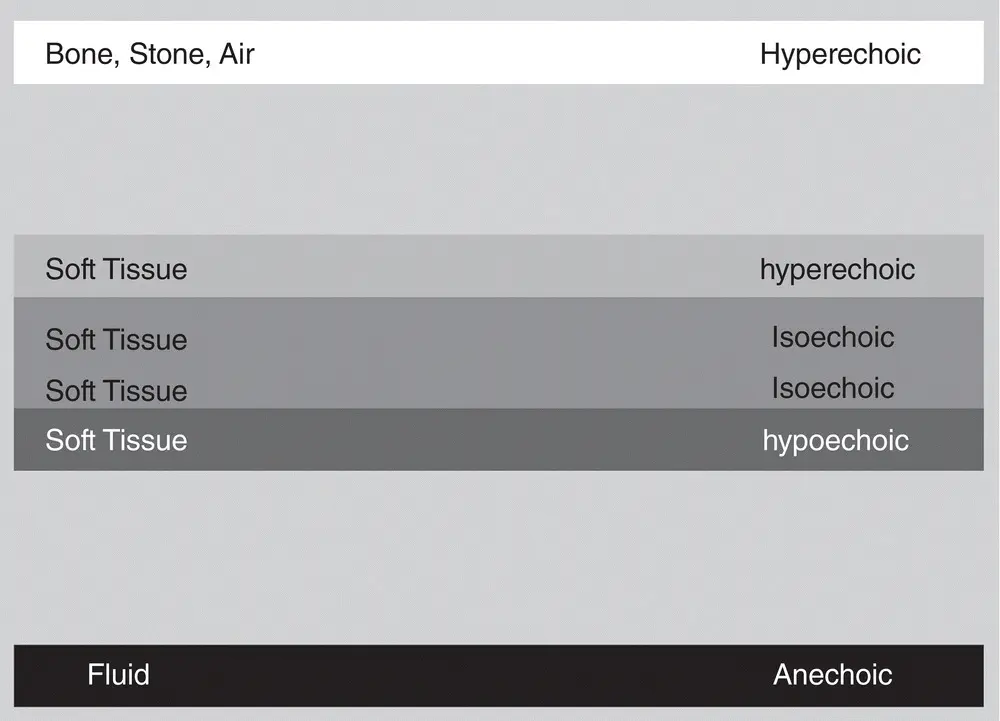

The ultrasound terms describing whites, grays, and blacks are anechoic (black), degrees of echogenicity (hypoechoic, shades of gray), and hyperechoic (white). The terms may be used relatively between structures like “X relative to Y” and “Y relative to Z.” For example, the spleen is hyper echoic (brighter than) to the left kidney. The liver is hypo echoic (darker than) to the falciform fat. The feline cortex of the kidney is isoechoic (same as) to the spleen (see Figure 1.3).

Figure 1.3. This figure is similar to Figure 1.2but with some of the gray scale removed to illustrate how descriptive ultrasound terminology is used for different tissues. The soft tissue is isoechoic (same as), hyperechoic (brighter than), and hypoechoic (darker than) relative to one another. Correlate with Table 1.1Courtesy of Dr Gregory Lisciandro, Hill Country Veterinary Specialists and FASTVet.com, Spicewood, TX.